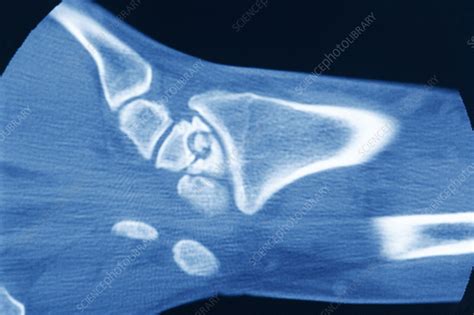

Alright, let’s talk about the symptoms and how pseudo artritis infectada is usually diagnosed. Recognizing the signs is a big deal because the earlier you catch the problem, the better. Common symptoms include joint pain, especially when you move the affected area. The joint can also be tender to the touch. Sometimes, you might notice swelling, redness, and warmth around the joint. You can feel the heat with your own hand. Fever is also common, as your body tries to fight off the infection. Other symptoms include difficulty moving the joint and feeling generally unwell, such as fatigue or a loss of appetite. Now, the symptoms of pseudo artritis infectada can sometimes mimic other conditions. The process of getting a diagnosis can involve a combination of approaches. The doctor will begin with a thorough examination, going through your medical history and doing a physical checkup. They’ll ask about your symptoms, look for any signs of infection (like redness, swelling, and warmth around the joint), and assess how well your joint moves. Next, they will probably order imaging tests like X-rays or MRI scans. These tests can help rule out other problems and look for signs of inflammation or damage inside the joint. The main test is a sample from the joint, called arthrocentesis, which involves drawing fluid from the joint. This fluid can then be analyzed in the lab. It is then tested for bacteria or other germs. Getting the right diagnosis involves combining a medical history, physical examination, imaging tests, and lab analysis. It is essential to recognize the symptoms of pseudo artritis infectada early and see a doctor right away if you think you might have the condition.